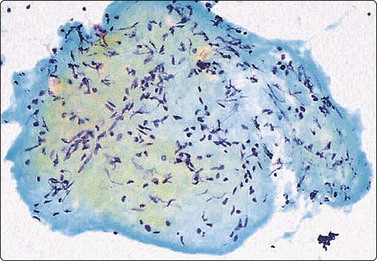

Fig. 7.2 Non-neoplastic glandular breast tissue and low-grade duct carcinoma

Low-power view; (A) Bimodal population of epithelial sheets and single bipolar nuclei of non-neoplastic glandular breast tissue; (B) Single population of epithelial cells in low-grade carcinoma (MGG, LP).